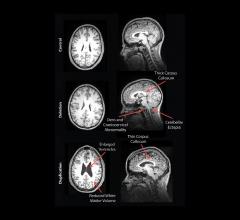

GE Healthcare announced Signa Premier, a new wide bore 3.0T magnetic resonance imaging (MRI) system, is now available for sale in the United States. Signa Premier is the result of a four-year collaboration with the National Football League (NFL) and research institutions around the world working to design new imaging tools, particularly to aid researchers in the detection of biomarkers for the potential diagnosis of mild traumatic brain injury (TBI). GE said the system delivers a new level of clinical performance with additional research-focused capabilities, especially for neurology and oncology research.